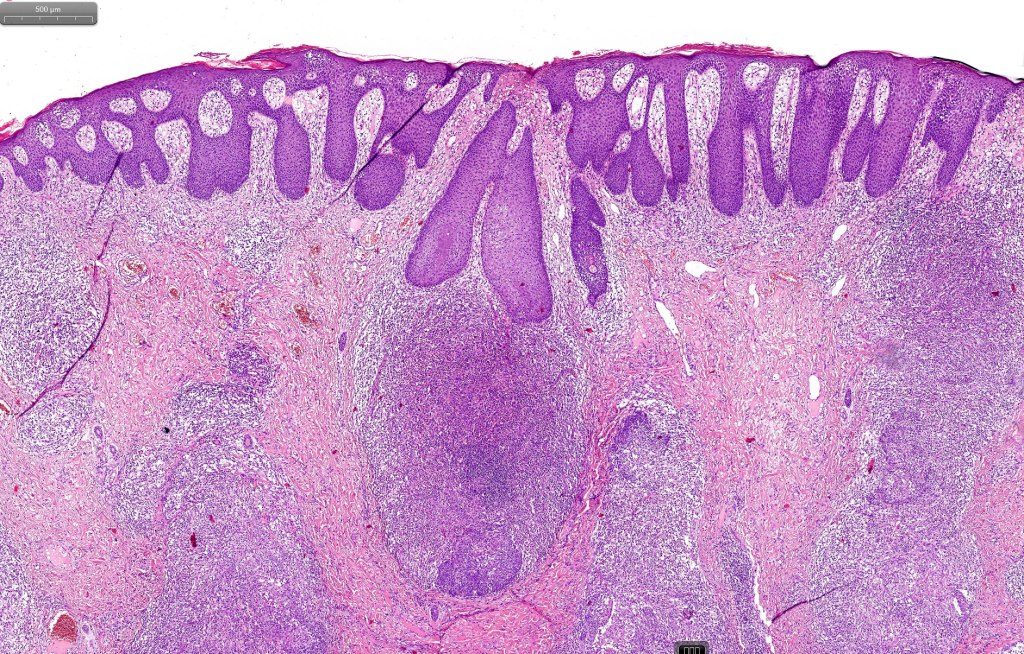

Histological features

•Epidermal involvement often absent

•Follicular infiltration by atypical lymphocytes & Sézary cells

•+/- mucinosis

•+/- basaloid follicular hyperplasia